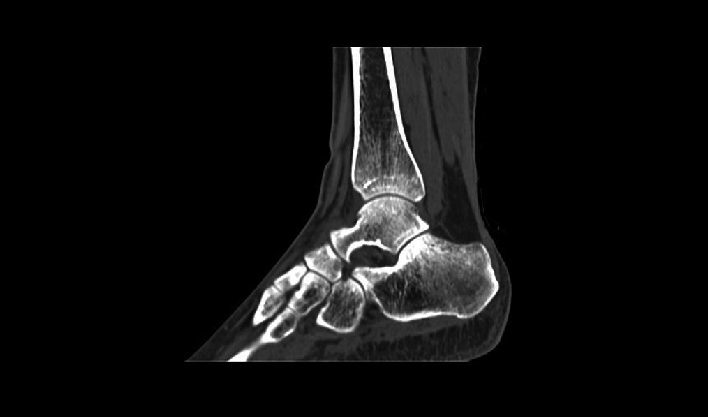

La matriz de reconstrucción de 1024*1024 amplía los datos de la imagen cuatro veces. Combinado con imágenes de corte fina, incluso las lesiones más invisibles son claramente visibles.